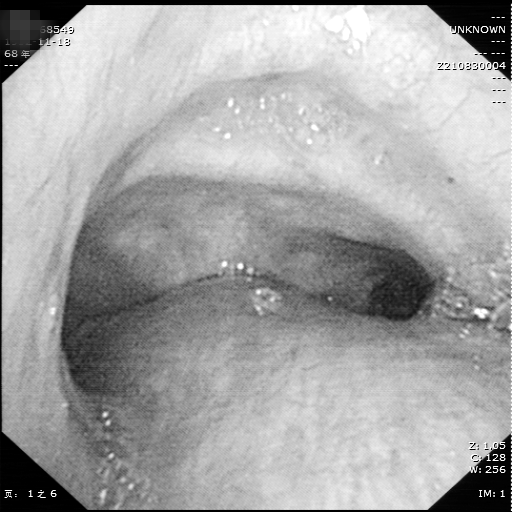

因病因无法明确,且刘大爷一直反复咯血,为求诊治,特地来到湘雅常德医院呼吸内科就诊。入院后,周政副主任医师及李儒鹏副主任医师详细询问病史、仔细查阅外院CT片及支气管镜检查结果后认为:患者胸部CT示纵膈淋巴结明显肿大,可经支气管镜针吸活检明确诊断。与患者及家属商量后,决定为患者行电子支气管镜检查,检查过程中发现右主支气管病变并活动性出血,气管下段黏膜明显隆起,结合胸部CT,两位副主任医师决定为患者进行气管后淋巴结(3P组)经支气管针吸活检术(TBNA)获取淋巴结组织标本。随后,将获取的标本立即制片染色后置于显微镜下观察,立刻送至病理科进行细胞病理学检查,结合右主支气管活检标本病理及免疫组化,最终确诊为:肺鳞癌。

气管下段粘膜隆起